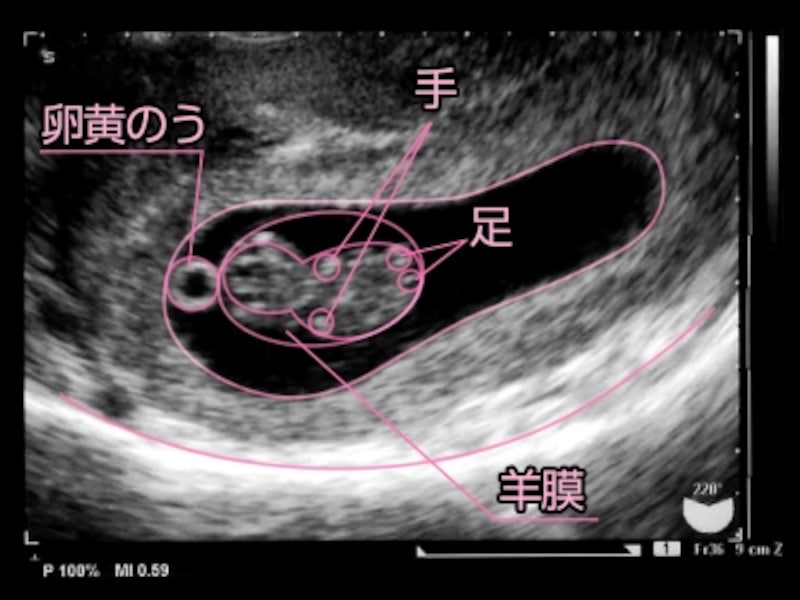

11週目エコー うごうごwww Youtube

妊娠11週目 11w0d 6d のエコー写真とエピソード 妊娠3ヶ月 Cozre コズレ 子育てマガジン

医師監修 妊娠11週のエコー写真を多数掲載 みんなのエピソードつき マイナビウーマン子育て

医師監修 妊娠11週のエコー写真を多数掲載 みんなのエピソードつき マイナビウーマン子育て

妊娠11週1日 11w1d の超音波 エコー 写真

妊娠11週4日 11w4d の超音波 エコー 写真